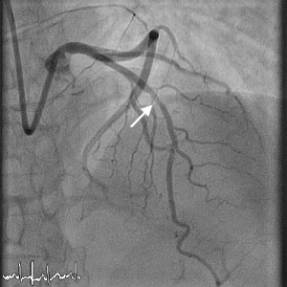

Left main stem (LMS) stenting

Left main stem…